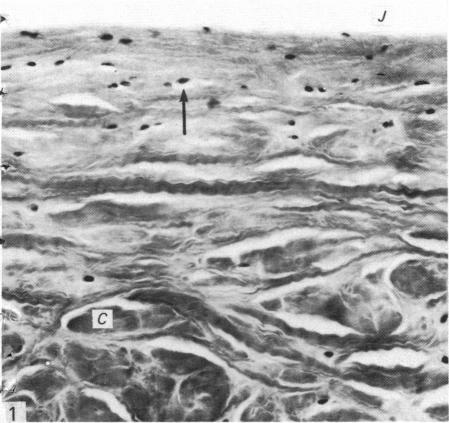

Normal human menisci obtained at autopsy (seven cases) and the injured and uninjured portions of torn menisci obtained at surgery (nine cases) were studied with the electron microscope. The surface of menisci is composed of collagen fibrils surmounted by an electron-dense surface coat. Most of the cells in menisci are chondrocytes but a few fibroblasts and cells of an intermediate form difficult to classify as either fibroblasts or chondrocytes also occur. Mast cells are found at the vascularised periphery of the meniscus. Myofibroblasts were found in the injured portions of menisci in three out of the nine cases studied. A territorial matrix containing fibrils and proteoglycan particles with associated filaments is seen around or adjacent to chondrocytes, but sometimes this matrix is sparse or absent. The interterritorial or general matrix comprises collagen fibrils of widely varying diameters (25-180 nm) set in a sparse interfibrillary matrix containing proteoglycan particles. A few mature elastic fibres and several small or immature elastic fibres and collections of electron-dense filaments are seen in the general matrix. Also seen in this region are calcified bodies and matrical lipidic debris derived by the shedding of cell processes and in situ necrosis of cells. Other features seen in the matrix of the injured portion of the meniscus include: (1) membrane-bound cystic structures; (2) parting and fraying of collagen fibrils; and (3) pools of proteoglycan particles.

对尸检获得的正常人类半月板(7例)以及手术中获得的撕裂半月板的损伤和未损伤部分(9例)进行了电子显微镜研究。半月板表面由胶原纤维组成,其上方有一层电子致密的表面涂层。半月板中的大多数细胞是软骨细胞,但也有一些成纤维细胞以及难以归类为成纤维细胞或软骨细胞的中间形态细胞。在半月板血管化的周边发现了肥大细胞。在所研究的9例中,有3例在半月板的损伤部分发现了肌成纤维细胞。在软骨细胞周围或附近可见到一个含纤维和蛋白聚糖颗粒以及相关细丝的区域基质,但有时这种基质稀疏或不存在。区域间或一般基质由直径差异很大(25 - 180纳米)的胶原纤维组成,这些纤维分布在含有蛋白聚糖颗粒的稀疏纤维间基质中。在一般基质中可见到一些成熟的弹性纤维、几条小的或不成熟的弹性纤维以及电子致密细丝的聚集物。在该区域还可见到钙化小体以及由细胞突起脱落和细胞原位坏死产生的基质脂质碎片。在半月板损伤部分的基质中还可见到其他特征:(1)膜结合的囊性结构;(2)胶原纤维的分离和磨损;(3)蛋白聚糖颗粒池。